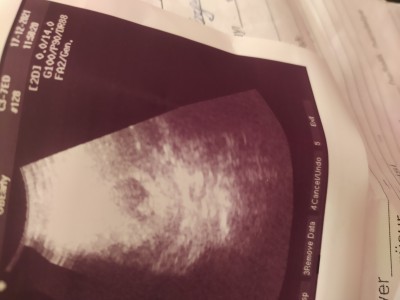

Merhaba kizlar benim ultrason goruntume bakarmisiniz bu arada Azerbaycanliyim 11  haftalik hamileyim 3 hafta once doktora gitmiwdim yani 8 haftada hamileliyim icin tabi devlete gitdim kalp atiwini devlette dinletmiyolar iyide bakmiyorlar sadece dediler gebelik var kalp atiwida var ama dinletilmiyor benim ultarson resmine bi bakarmisiniz ben 2 kese goruyorumda sizcede iki tanemi bir tanemi

Gebelik haftası 11 hafta

Canım benim de 8 haftalıkken böyle görünüyordu tek bence ama keşke doktora tek mi diye sorsaydın bu arada bir kere de olsa dinlemek için bence özele git

Tek kese gördüm bn cnm

keseniz bi tane ve bebeginiz de içinde gozukuyo